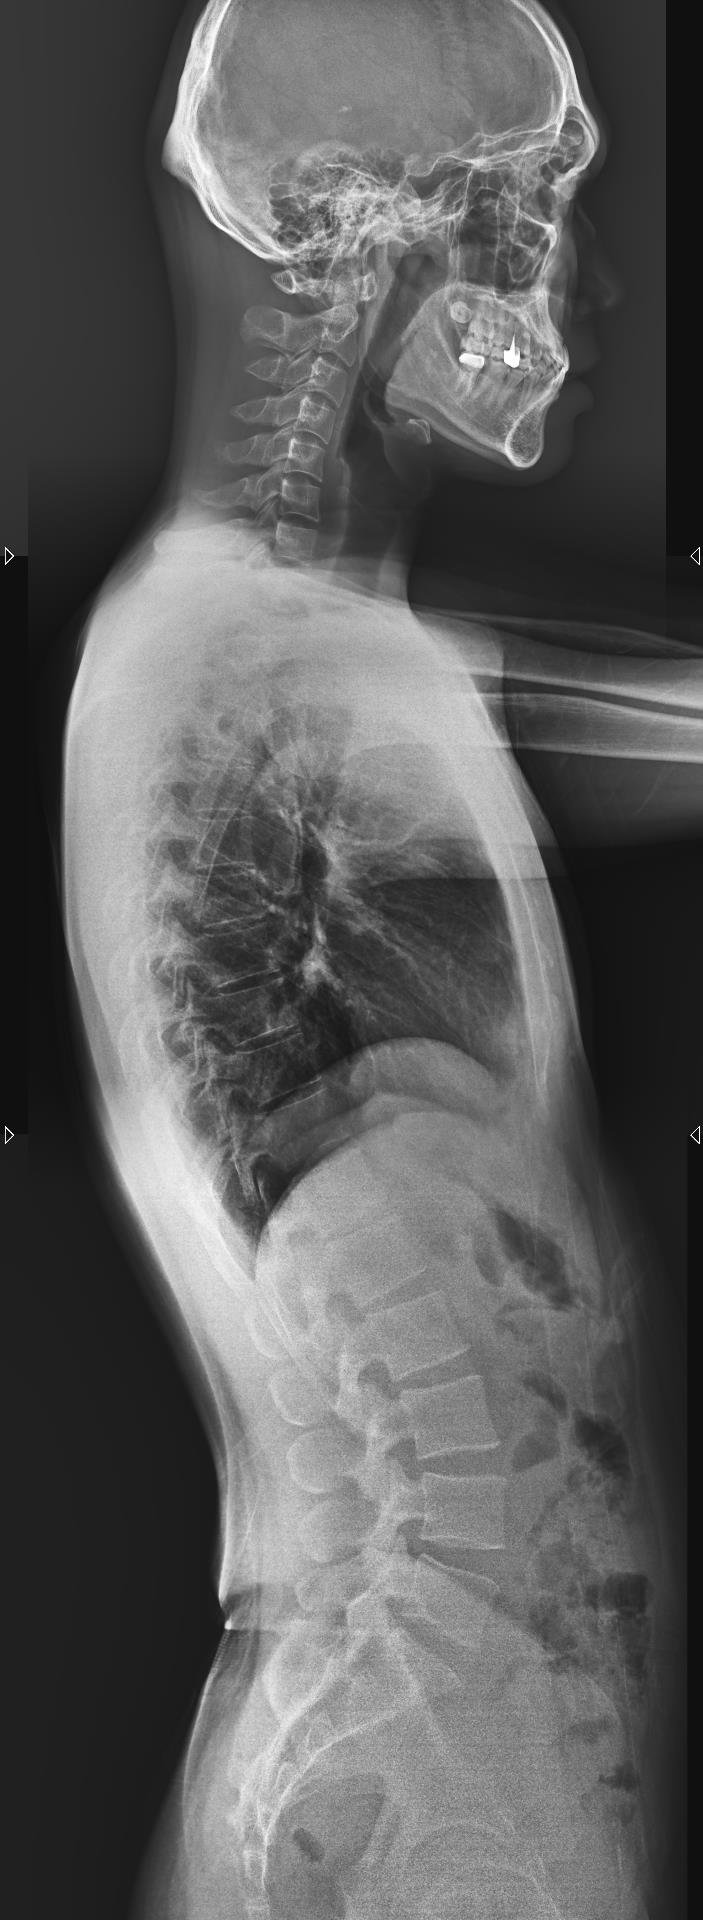

Ảnh chụp X-Quang cột sống (ảnh trên: một phần, ảnh dưới: toàn phần)

Chụp X-quang cột sống là kỹ thuật sử dụng tia X để ghi lại hình ảnh cấu trúc xương của cột sống, bao gồm các đốt sống cổ, ngực, thắt lưng và xương cùng. Với X-quang cột sống toàn phần, bác sĩ có thể quan sát cột sống như một chỉnh thể thống nhất, thay vì chỉ nhìn từng đoạn riêng lẻ.

Chụp X-quang toàn bộ cột sống là phương pháp chẩn đoán hình ảnh giúp bác sĩ đánh giá tổng thể cấu trúc xương sống, từ đó phát hiện sớm nhiều bất thường và bệnh lý quan trọng. Thay vì chỉ quan sát từng đoạn riêng lẻ, kỹ thuật này cho phép nhìn cột sống như một chỉnh thể thống nhất, phản ánh đúng trục chịu lực và sự liên kết giữa các vùng cổ – ngực – thắt lưng – xương cùng.

Hình ảnh X-quang toàn bộ cột sống được ghi nhận ở nhiều tư thế, nhiều góc độ, giúp bác sĩ: